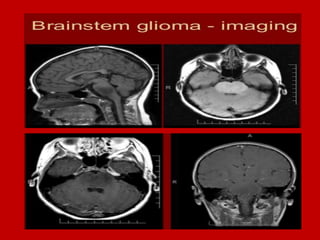

Brain Stem Lesions.

Glioma.